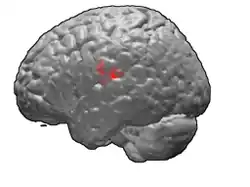

Brodmann area 43

Brodmann area 43, the subcentral area, is a structurally distinct area of the cerebral cortex defined on the basis of cytoarchitecture. Along with Brodmann Area 1, 2, and 3, Brodmann area 43 is a subdivision of the postcentral region of the brain,[1] suggesting a somatosensory ('feeling of the body') function. The histological structure of Area 43 was initially described by Korbinian Brodmann, but it was not labeled on his map of cortical areas.[2]

In the human subcentral area 43, a sub area of the cytoarchitecture is defined in the postcentral region of the cerebral cortex. It occupies the postcentral gyrus, which is between the ventrolateral extreme of the central sulcus and the depth of the lateral sulcus, at the insula. Its rostral and caudal borders are approximated by the anterior subcentral sulcus and the posterior subcentral sulcus, respectively. Cytoarchitecturally, it is bounded rostrally, by the agranular frontal area 6, and caudally, for the most part, by the caudal postcentral area 2 and the supramarginal area 40.[1]